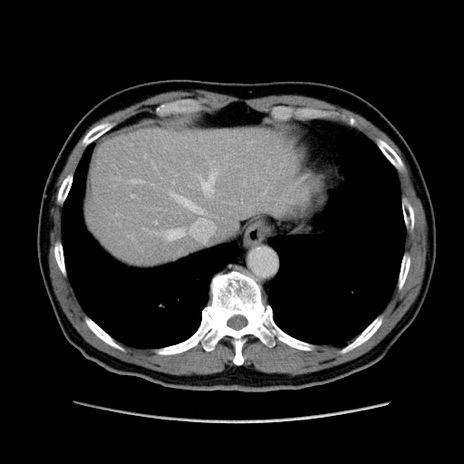

矢状断像